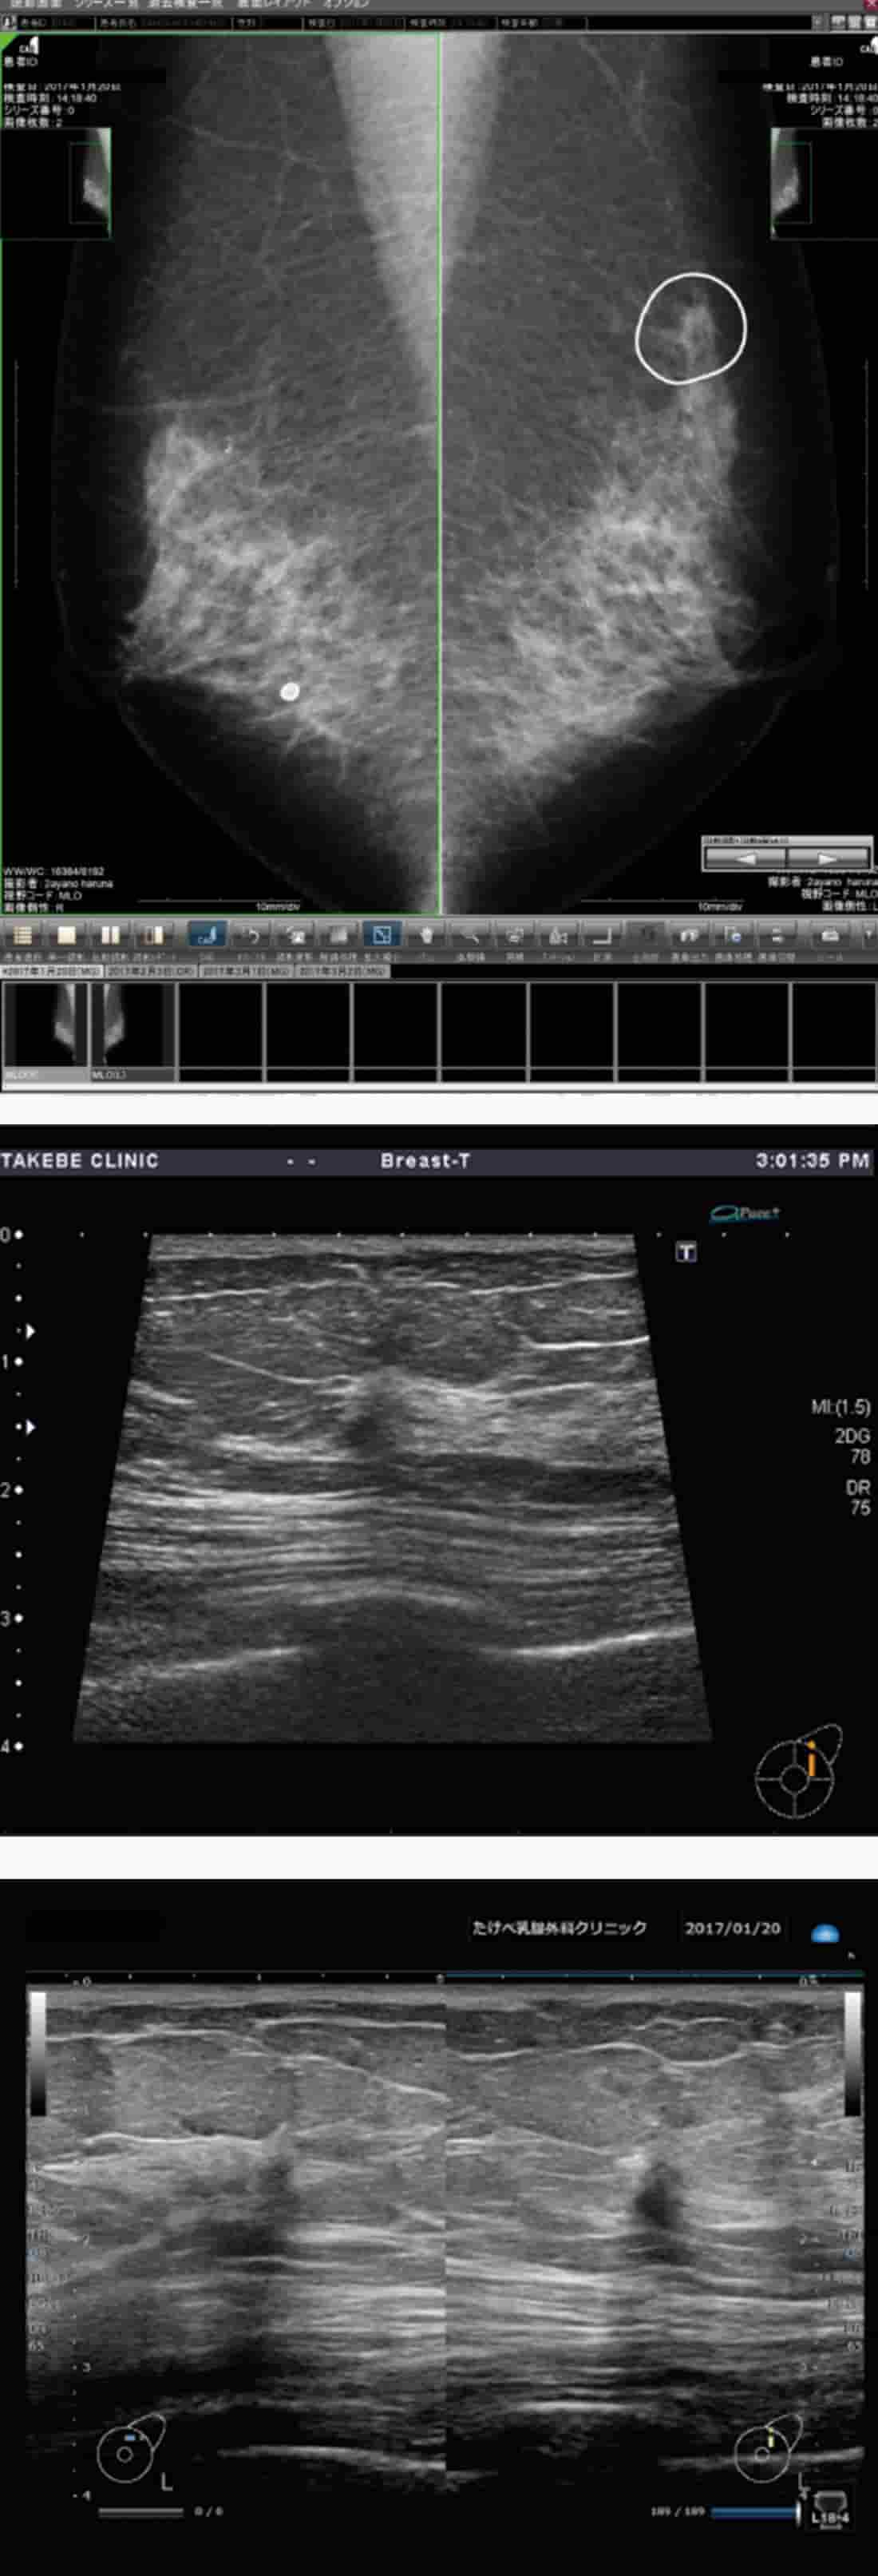

マンモグラフィ、超音波の画像(過去画像・CAD表示)をみながら、技師は隣のコニカミノルタの超音波診断装置SONIMAGE HS1で検査を実施し、超音波の所見をOsiriXに転送する(動画、静止画)。

当院では、2011年から2016年までに、21,623名の検診を実施しました。 マンモグラフィは、40歳代は2方向、50歳代は1方向で撮影しています。 検診の流れは、マンモグラフィ撮影→超音波を実施する技師がモニタ画面でマンモグラフィを読影(第1読影)→CADを参考にしてマンモグラフィ所見を記入→CADと自身の読影を参考に超音波にてwhole breast scanning後、超音波所見を記入、というものです。 医師は、マンモグラフィ読影(第2読影)と技師の超音波所見から総合的に判断し、要精査かどうかを決定します。過去画像もモニタで確認しながら行います。 超音波画像はOsiriX(オザイリクス)というイメージ処理ソフトウェアで管理し、過去の動画も含めて参照できるようにしています(図2)。 技師にはマンモグラフィを読影する際、必ずCADが指摘した箇所をすべて所見用紙に記入し、そのすべての所見を超音波で見るよう指導しています。 所見用紙には、要FNAC(穿刺吸引細胞診)、要医師判定、不要FNACの項目があり、基本的に当院では細胞診を第一選択としています。 検診成績は、要精査率が4.2%、無自覚の癌発見率が0.54%で、陽性反応適中度は、無自覚の癌でも13.8%です。

スクリーニングにおけるコニカミノルタの超音波診断装置「SONIMAGE HS1」(以下、HS1)の有用性は、強調差がある点です。 図4の症例は、左U領域にカテゴリー4または5の病変が認められたもので、CADはきちんと指摘しています。 HS1画像では低エコーが強調されて描出されます。小さな硬癌(scirrhous carcinoma)や、radial scar、invasive lobular carcinoma等では、このような強調差があるほうが医師は楽で、技師も見つけやすいです。スクリーニングではこのような強調差のある画像処理は有用であると考えます。 精査における有用性という点では、HS1では23Gの穿刺針の視認性が高く、プローブも小さくて軽いので使いやすいです。 耐久性も評価でき、薬剤などが付着してもビームの切れが少なく、超音波ガイド下での穿刺に適しています。

コニカミノルタのHS1では、石灰化は少しべったりして大きく見えます。慣れないと石灰化に見えないこともあるのですが、慣れれば十分見えてきます。 脂肪の中にある石灰化で、これまで見るのが大変難しかったものも、HS1では良く見えます。図5はカテゴリー4の石灰化が認められる症例です。 CADはしっかり指摘しており、HS1で良く描出されています。

CADはしっかり指摘している(a)。他社の超音画像(b)に比べ、HS1の画像(c)では低エコーが強調されて描出される

このような強調差があるほうが医師は楽で、技師も見つけやすい。

カテゴリー4の石灰化が認められる症例。CADはしっかり指摘しており(a)、HS1で良く描出されている(b)。